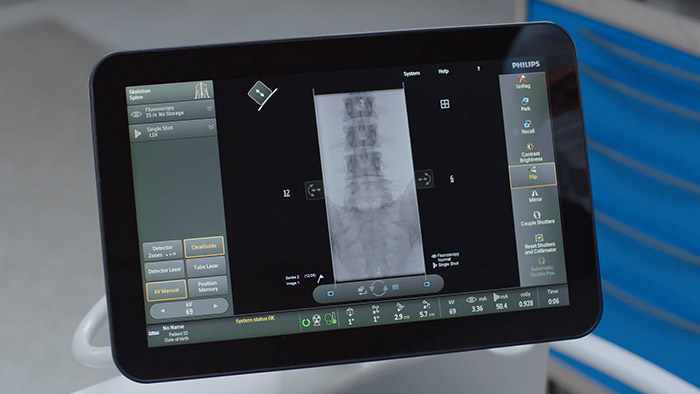

Módulo de pantalla táctil* El módulo de pantalla táctil (Touch screen module, TSM) está diseñado para ofrecer valor porque mejora las capacidades clínicas de Zenition 70. Como complemento de la plataforma Zenition 70, el TSM permite el control completo desde la mesa para los cirujanos durante los procedimientos. * El TSM está disponible como elemento opcional solo para Zenition 70.